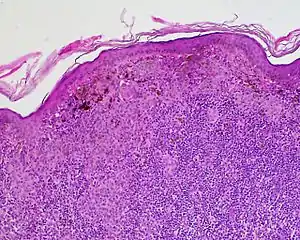

Halo nevus (also known as "Leukoderma acquisitum centrifugum," "Perinevoid vitiligo," and "Sutton nevus"[1]:689) is a mole that is surrounded by a depigmented ring or 'halo'.

Halo nevi are also known as Sutton's nevi, or leukoderma acquisitum centrifugum. Halo nevi are named such because they are a mole (nevus) that is surrounded by an area of depigmentation that resembles a halo.

The formation of a halo surrounding a nevi is believed to occur when certain white blood cells called CD8+ T lymphocytes destroy the pigment-producing cells of the skin (melanocytes).[2] The cause for the attack is unknown.[3]